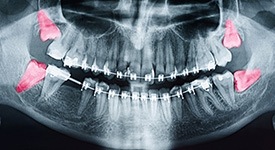

Wisdom teeth are the third set of molars. It’s believed that they earned the nickname due to the fact that they are the last to emerge (and wisdom comes with age). While they served a useful function a long time ago, they usually cause problems today due to there not being enough space in a patient’s mouth by the time they’re ready to erupt. As a result, they usually need to be removed.

If we do determine that your wisdom teeth are more harmful than helpful, then we will proceed with either a simple or surgical extraction. A simple extraction is ideal when the tooth in question has already broken through the gumline, allowing us to rock it loose until it’s ready to be removed. If it’s trapped underneath, however, then we will need to create a small incision in the gums to access it. Then, we can remove it section by section before tending to the extraction site.

- Whether or not your wisdom teeth are impacted. Impacted teeth cost more to remove. There are two types of impactions, soft tissue impaction occurs when the tooth or teeth have fully or partially emerged, while bony impaction requires the tooth to be removed from the jawbone.